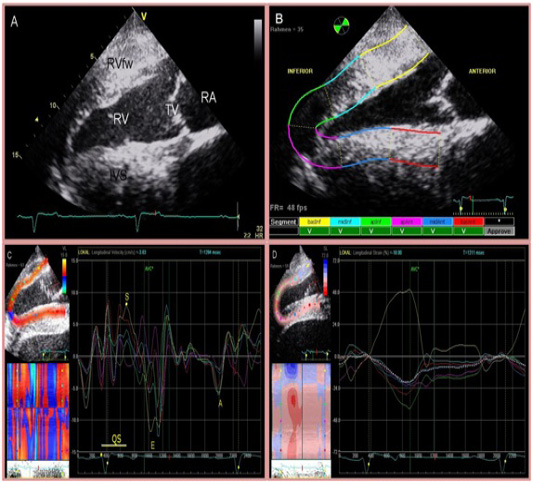

Four chamber view of the heart (A) and two-dimensional speckle tracking analysis (B). The right side of the image is cranial. Inferior is referred to as RV and anterior as IVS. The region of interest is manually divided into 6 segments starting at the IVS. Tracking quality is verified by the software and approved segments are marked with ‘V’. Segmental curves for long-axis images show the longitudinal velocity (C), and the longitudinal strain % (D). On the left, a greyscale image is displayed showing the tracked ROI. On the right, the segmental traces are displayed. The vertical axis represents values of the selected variable; the horizontal axis shows time (ms).